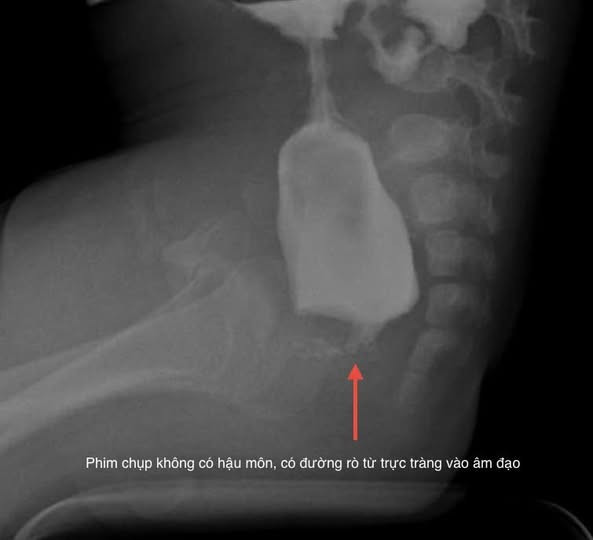

Mới đây, khoa Ngoại Tổng hợp vừa phẫu thuật nội soi cho một trẻ mắc dị tật không có hậu môn. Đây là một trường hợp rất đặc biệt, cháu Bùi Ngọc Kh. L địa chỉ tại An Lão, Hải Phòng, sau sinh đã phát hiện không có hậu môn, phân dò ra qua đường âm đạo.

Gia đình thấy trẻ vẫn ăn uống bình thường, hàng ngày vẫn thấy có phân ra nên không đi khám theo hẹn, gần đây trẻ thường xuyên chướng bụng, không thấy phân ra nên gia đình cho đi khám.

Các bác sĩ tiếp nhận trẻ trong tình trạng suy dinh dưỡng, thiếu máu, có dị tật tiết niệu và rối loạn nhịp tim kèm theo, đại tràng sau quá trình ứ phân kéo dài bị giãn.